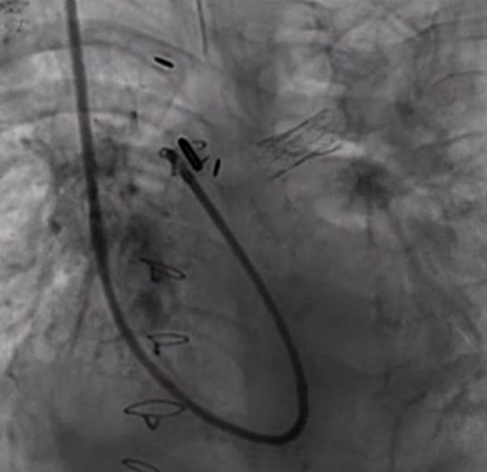

從右側開始,Ing的團隊能夠使用氣球打開堵塞。然而,對於左側,他們需要支架。由於Nate的左肺動脈狹窄至僅為15mm,Ing博士采取了特殊措施,他小心地切開醫院最小的現有支架,並使用他的團隊開發的特殊技術將其折回自身,並有效地定製功能性定製支架。

到2017年1月,Nate終於準備好了下一個心髒手術。1月19日,Ing博士插入了第二個甚至更小的支架,他塑造了Nate右肺動脈的3D打印模型。開放心髒手術在洛杉磯兒童醫院導尿實驗室進行,大量的國際心髒病學家通過實況視頻觀看。Ing博士和他的團隊成功地開放了Nate的右肺動脈。嬰兒的氧氣水平幾乎立即改善,相比以前,這種情況幾乎沒有治愈的希望。